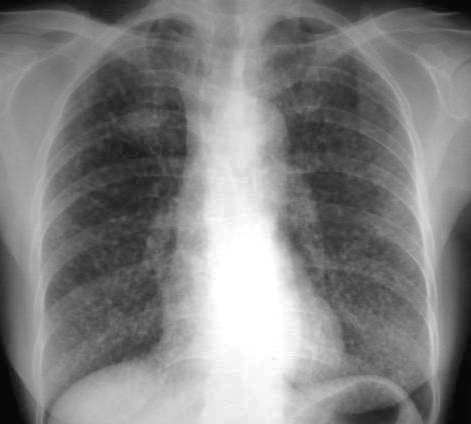

黄某,女,66岁,胸闷、咳嗽1个月,近日体重减轻。请讨论

两肺见弥漫分布的小粟粒状影,考虑:1、血播tb;2、肺泡细泡癌;3、肺内转移病变。

两肺弥漫均匀分布的粟粒状影:1.急性血行播散性肺结核;2.支气管肺泡癌待排

右肺上叶斑块状影,双肺弥漫分布多发小结节影,以双下肺叶为著。

考虑:1、右侧肺癌并双肺内血行转移。

2、肺泡细胞癌。

3、不除外血行播散型肺结核,建议结合临床查痰或做结核菌素实验。

右肺上叶类圆影,两肺小结节影,结合临床考虑右上肺癌伴肺内转移可能性大。